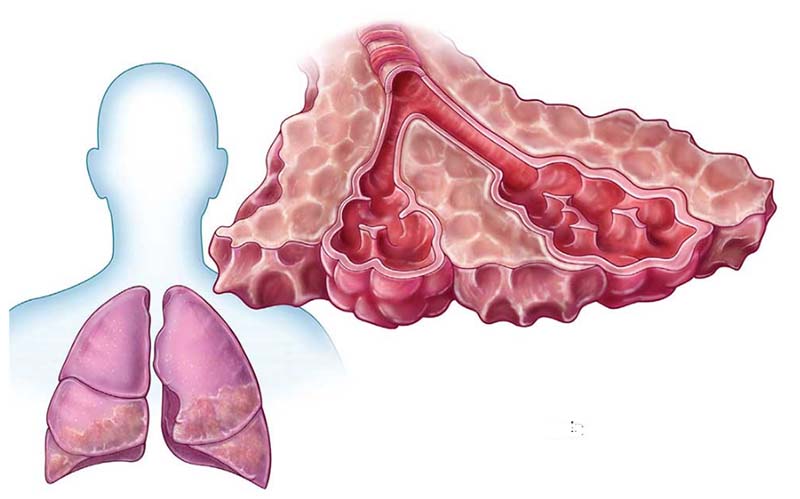

Xơ phổi là căn bệnh thường gặp hiện nay và nhiều người mắc phải. Vậy xơ phổi có nguy hiểm không và cách điều trị ra sao là câu hỏi của nhiều người. Xơ phổi là tình trạng các mô bên trong phổi bị tổn thương mãn tính khiến cho các mô phổi dày lên, cứng hơn do bị mất tính đàn hồi, từ đó gây ra sẹo. Phổi bị xơ sẹo và cứng nên làm hạn chế khả năng hít thở của người bệnh. Dưới đây chúng ta cùng...

Xơ phổi là tình trạng nhiều người gặp phải hiện nay và cũng có nhiều thắc mắc về căn bệnh này. Vậy xơ phổi là gì và cách điều trị ra sao là câu hỏi của nhiều người. Xơ phổi xảy ra khi các mô phổi bị tổn thương nhiều lần dẫn tới xơ hóa, ảnh hưởng và làm suy giảm chức năng của cơ quan này. Phổi bị xơ sẹo và cứng nên làm hạn chế khả năng hít thở của người bệnh. Dưới đây chúng ta cùng đi...